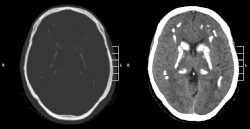

| CT scan of characteristic calcifications of the disease | |

Primary familial brain calcification[1] (PFBC), also known as familial idiopathic basal ganglia calcification (FIBGC) and Fahr's disease,[1] is a rare,[2] genetically dominant or recessive, inherited neurological disorder characterized by abnormal deposits of calcium in areas of the brain that control movement. Through the use of CT scans, calcifications are seen primarily in the basal ganglia and in other areas such as the cerebral cortex.[3]

Brain CT scan is the preferred method of localizing and assessing the extent of cerebral calcifications.

The calcification is usually identified on CT scan but may be visible on plain films of the skull.